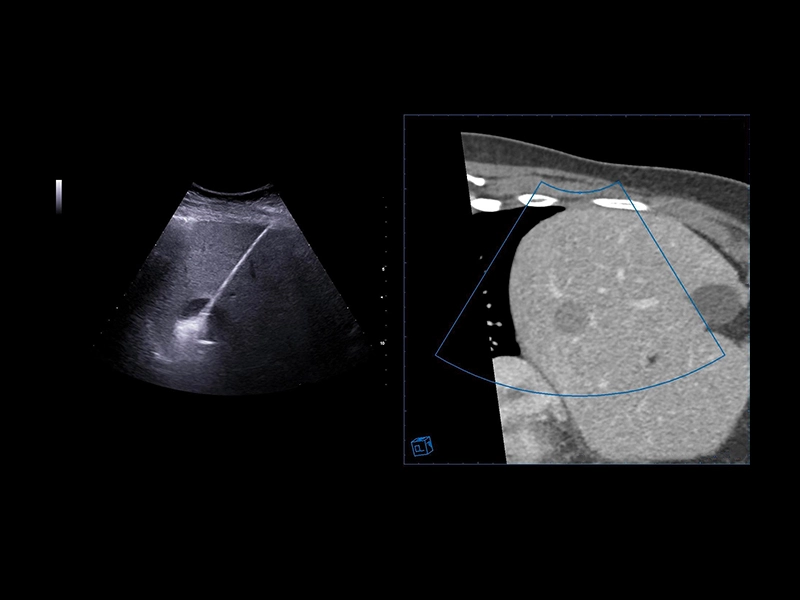

MyLab™E80 - VNav - Liver Fusion

MyLab™E80 - VNav - Liver Fusion

MyLab™E80 - LiverFusion

MyLab™E80 - LiverFusion

MyLab™9 Platform - Precise lesion detection and guidance with Virtual Biopsy

MyLab™9 Platform - Precise lesion detection and guidance with Virtual Biopsy

MyLab™Sigma Elite - Follow Up in real-time with a second modality

MyLab™Sigma Elite - Follow Up in real-time with a second modality

MyLab™X8 Platform - Prostate biopsy with Virtual Navigator fusion imaging 3D

MyLab™X8 Platform - Prostate biopsy with Virtual Navigator fusion imaging 3D